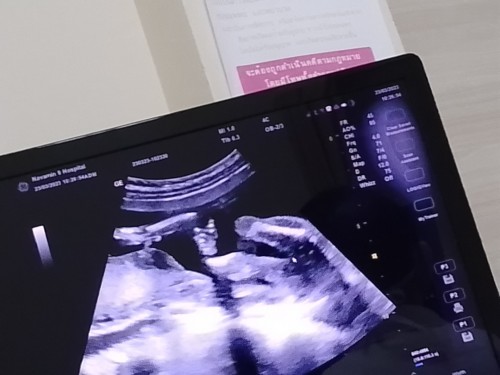

เมื่อวานไปอัลตร้าซาวด์มา หมอ บอกว่าได้ผู้หญิง แต่เราดูไม่ออกเลย แม่ๆท่านอื่นช่วยบอกหน่อยได้ไหมคะ

รูปแรกตรงที่ลูกศรชี้เป็นรูปหว่างขาน้องค่ะ ไม่มีอะไรยื่นๆ ออกมา น้องเป็นผู้หญิงค่ะ 😊